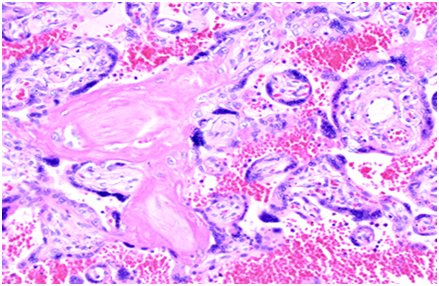

Placental fibrin deposit in FGR treated by heparin

Placental GLHW of a case of IUGR (fetal growth restriction, FGR) was larger than that of normal placenta and diagnosed by Utsu to be intervillous fibrin deposit (Figure 3) due to positive cardiolipin antigen in the pregnant woman, and daily 5,000 unit heparin was administered to the woman. The GLHW decreased, estimated fetal weight increased to normal, and normal neonate was obtained (Figure 4),3 despite an FGR fetus died in previous pregnancy of the mother in the present study.3 Discussion: The deposited fibrin would reduce placental active transfer of fetal nourishing material developing FGR, and further damaged passive transfer of oxygen would cause fetal demise in previous pregnancy. Heparin solved deposited fibrin to promote placental transfer function then treated FGR and prevented fetal demise after hypoxia.

Figure 3 Microscopic view of a placental intervillous space fibrin deposit. HE, 200x.